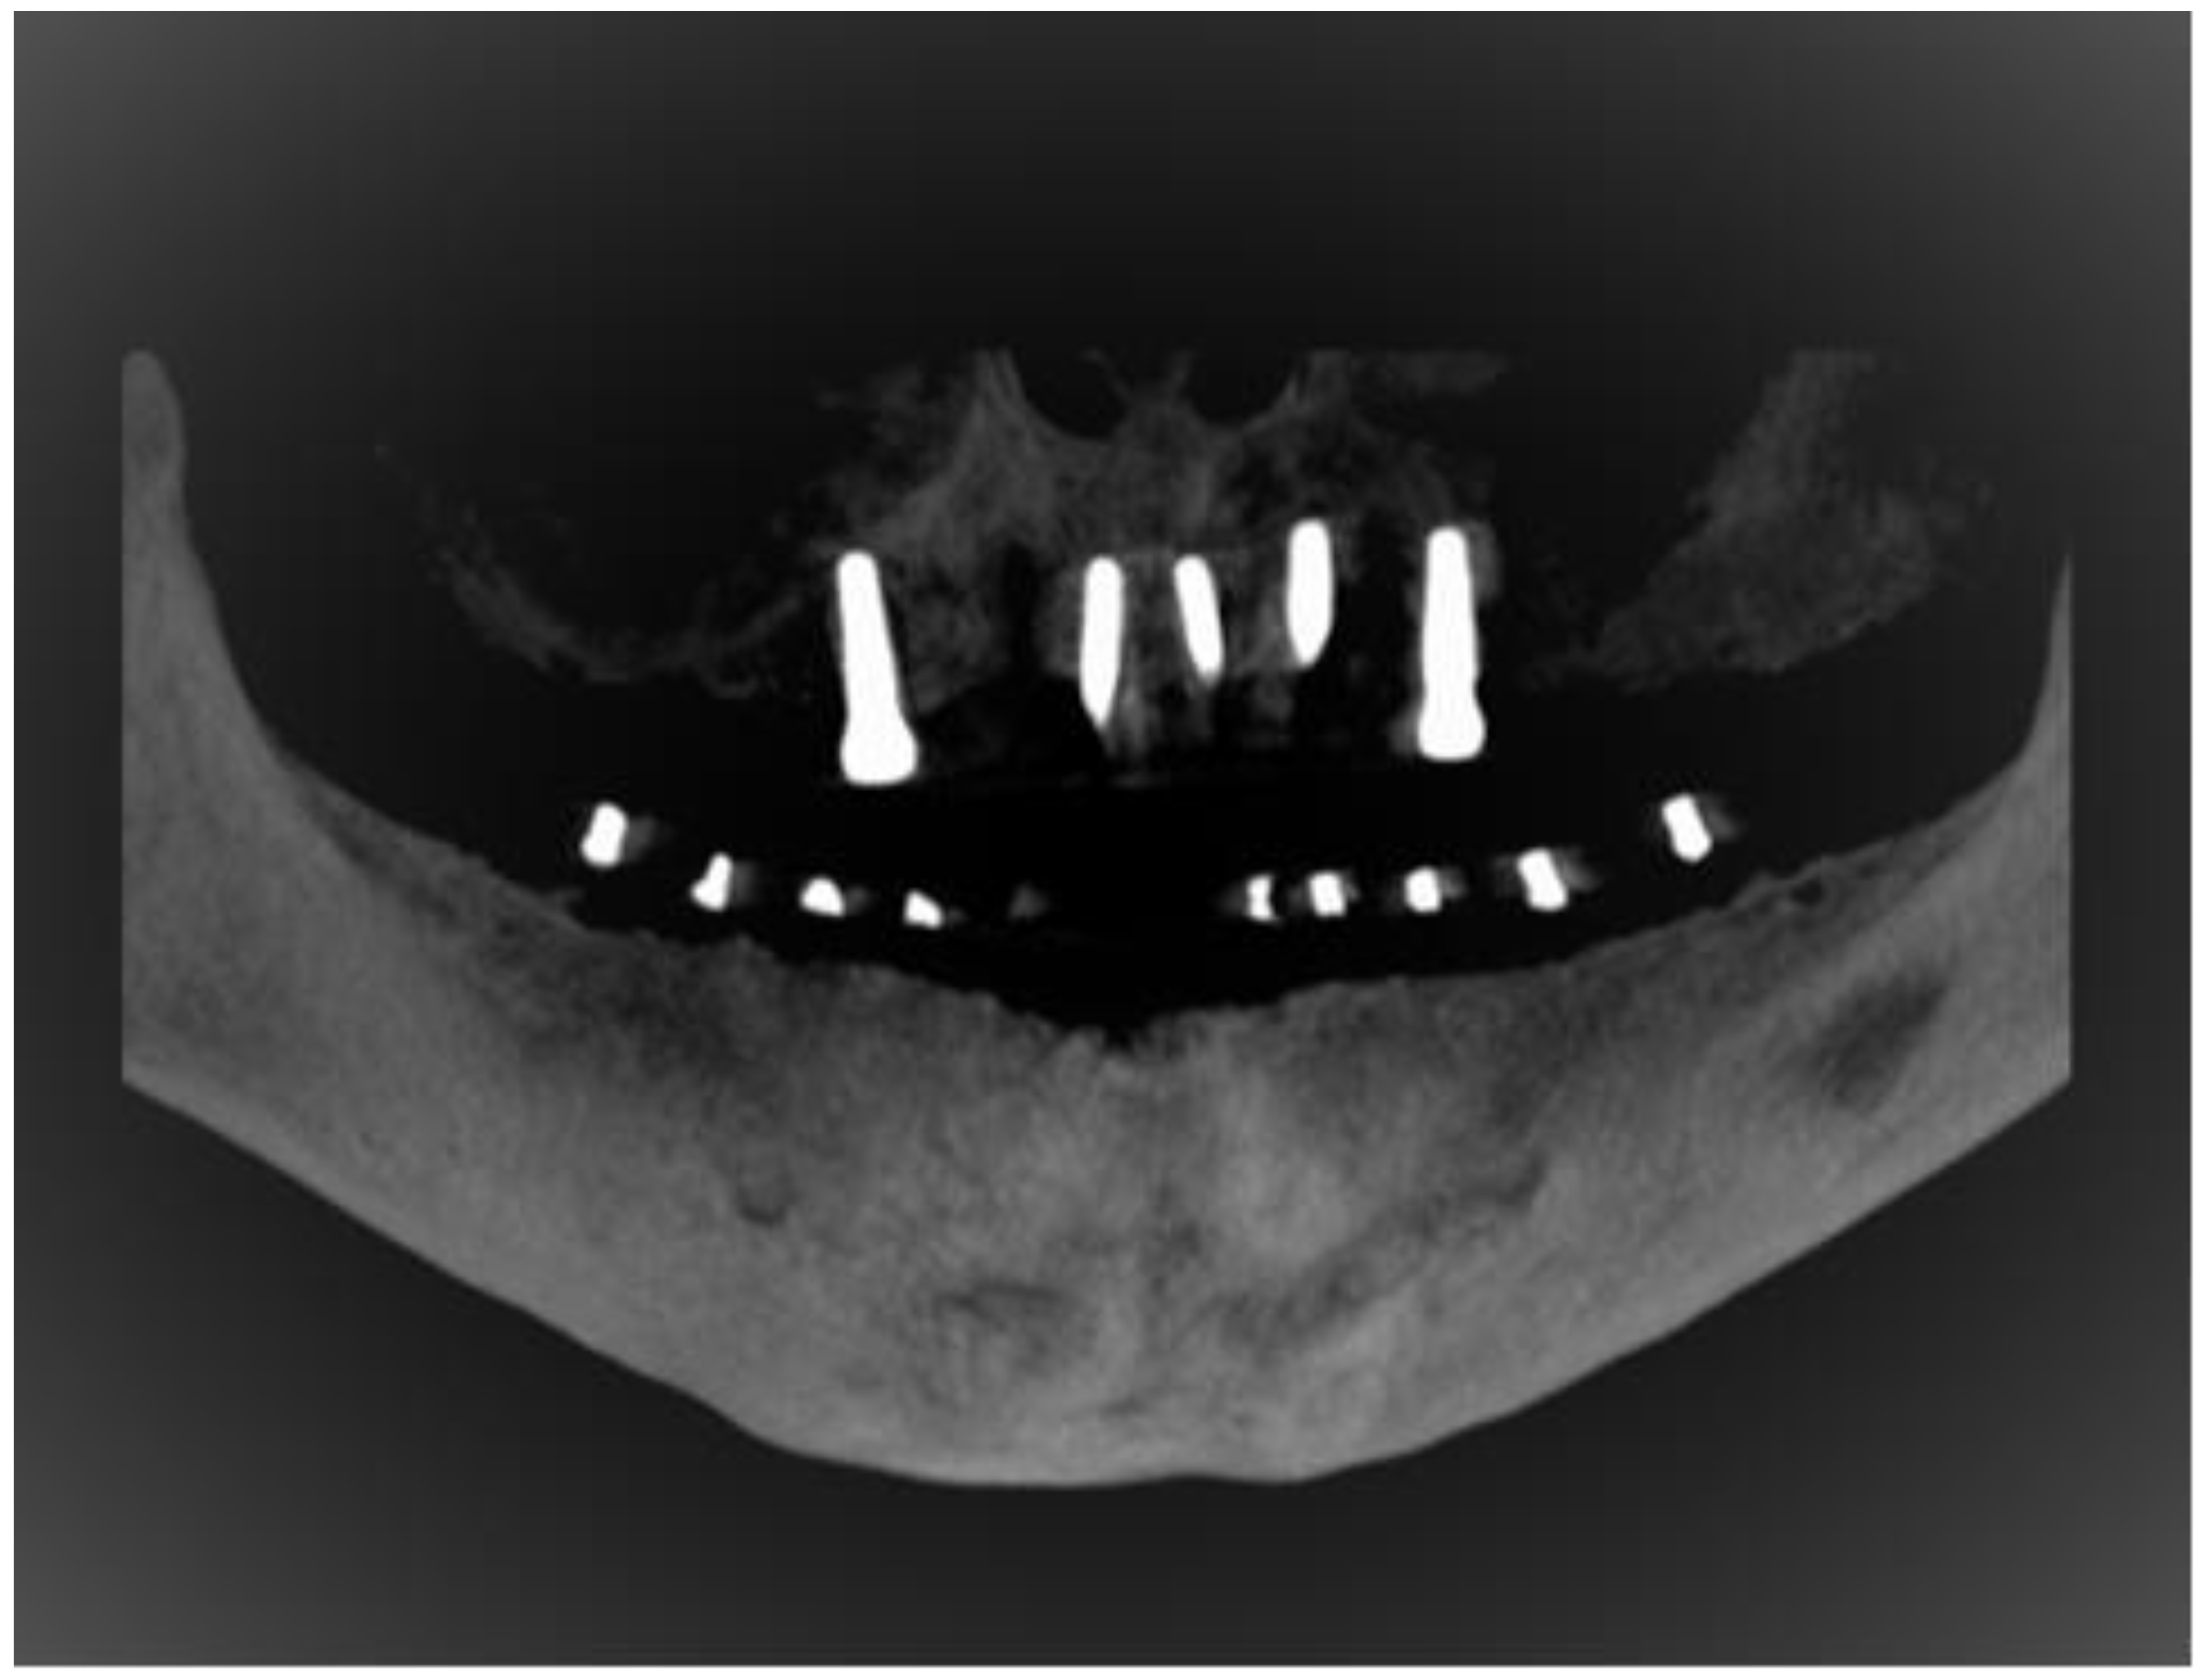

2.4. Study Protocol and Image Analysis

- Buccalcortical plate to IAN dimension (BCPN): Linear distance from the IAN to the nearest corresponding buccal outer cortical plate.

- Lingual cortical plate to IAN dimension (LCPN): Linear distance from the IAN to the nearest corresponding lingual outer cortical plate.

- Alveolar crest to IAN dimension (ACN): Linear distance from the IAN coronally to the midpoint of alveolar crest bone corresponding to the long axis of tooth.